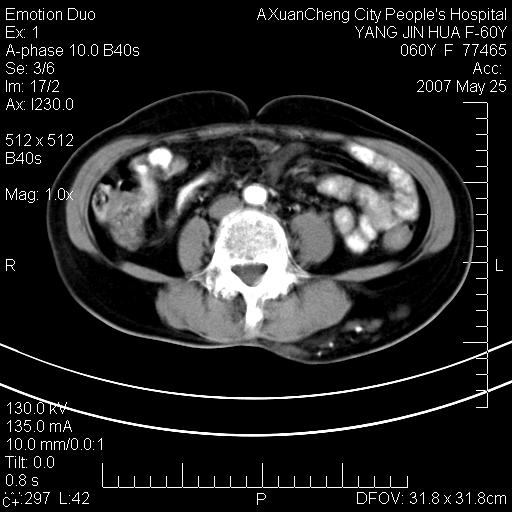

发现左侧腰背部包块40余年,逐渐长大,质软,局部表面可见扩张的血管影

左背部皮下良性肿瘤,密度不均,边界不清,内有脂肪、钙化,增强扫描无明显强化,血管平滑肌脂肪瘤?进一步诊断有困难,建议穿刺活检。

左侧背部皮下混杂密度肿块,结构较疏松,边缘欠光整,内有多发斑点状钙化,考虑:皮下血管瘤。

这个病理增强扫描之前,我们是考虑是血管瘤,可是现在增强后一点强化都没有,还能考虑是血管瘤吗